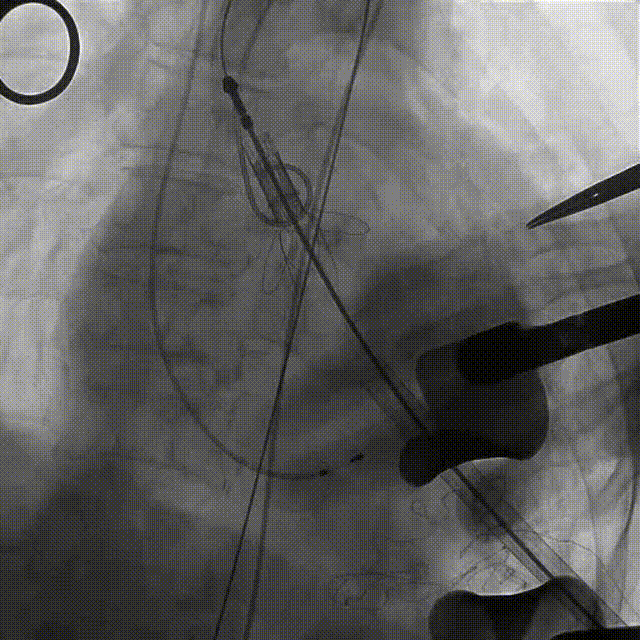

近日,中国人民解放军南部战区总医院王显悦教授、张本教授团队应用J-VALVE瓣膜完成一例高难度经心尖TAVI。患者为72岁男性,心脏超声示主动脉瓣重度狭窄伴轻度关闭不全,且二尖瓣中度狭窄。由于具有急性心力衰竭、高血压3级、肺气肿等其他疾病,且体重仅35公斤,对外科开胸手术耐受较差,风险极大,经过团队综合评估,决定行经心尖TAVI手术,拟植入25mm J-VALVE瓣膜。该患者存在升主动脉瓷化和左室流出道重度钙化,为手术增加了额外难度,术者团队凭借过硬的专业技能和细节处理能力,有效避免了术中可能存在的风险,并成功植入瓣膜。术后食道超声示无瓣周漏、无冠脉堵塞等并发症,患者症状明显缓解,手术顺利完成。

手术过程